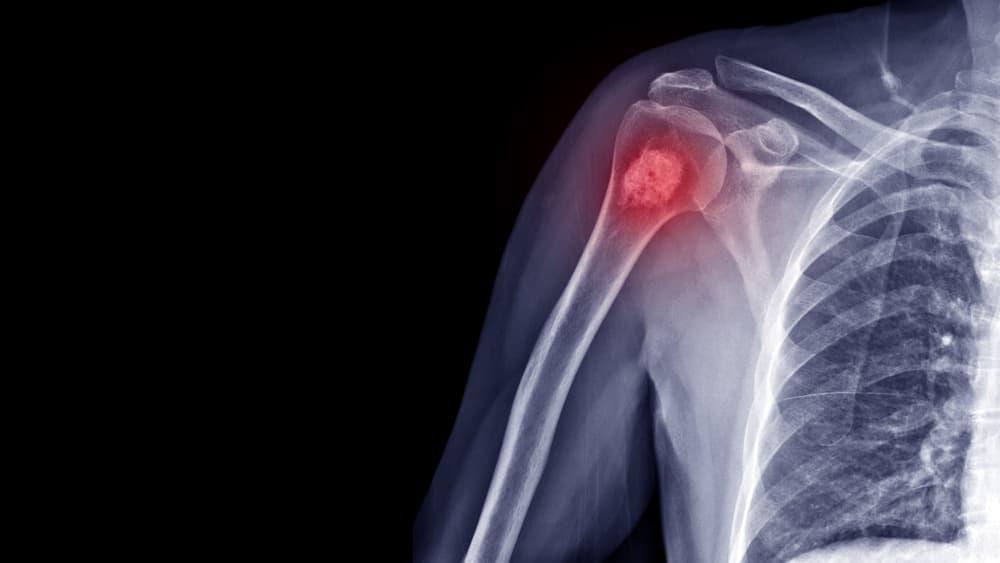

Bệnh u xương là gì? Các khối u xương phát triển khi các tế bào trong xương phân chia, phát triển không kiểm soát, tạo thành một cục hoặc khối u bất thường.

Một số khối u xương là ác tính (ung thư xương). Các khối u xương có thể ảnh hưởng đến bất kỳ xương nào trong cơ thể và phát triển ở bất kỳ phần nào của xương, từ bề mặt đến trung tâm của xương, được gọi là tủy xương. Bị u xương có nguy hiểm không? Các khối u xương ác tính có thể di căn hoặc khiến các tế bào ung thư lan rộng khắp cơ thể. Trong hầu hết các trường hợp, điều trị khối u ác tính bao gồm sự kết hợp của hóa trị, xạ trị và phẫu thuật.

Đôi khi, các khối u lành tính có thể được phát hiện tình cờ khi chụp X-quang vì một lý do khác, chẳng hạn như bong gân mắt cá chân hoặc chấn thương đầu gối.

Nhiễm trùng, gãy xương do căng thẳng và các tình trạng không phải khối u khác đều có thể gần giống với khối u. Để chắc chắn bạn có khối u xương, bác sĩ sẽ tiến hành đánh giá kỹ lưỡng và yêu cầu làm một số xét nghiệm.

- Chụp X-quang. X-quang cung cấp hình ảnh của các cấu trúc dày đặc, chẳng hạn như xương. Trong hầu hết các trường hợp, bác sĩ sẽ yêu cầu chụp X-quang để giúp chẩn đoán khối u xương. Các loại khối u khác nhau có thể trông khác nhau trên hình ảnh chụp X-quang. Một số làm tiêu xương, tạo lỗ trên xương hoặc xương mới hình thành (còn gọi là tạo xương).